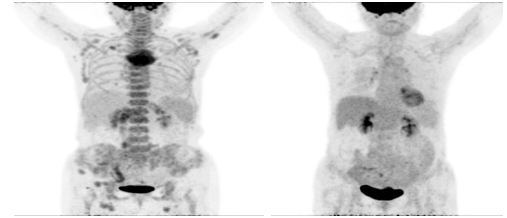

淋巴瘤治疗后2021-2-25 2021-7-24